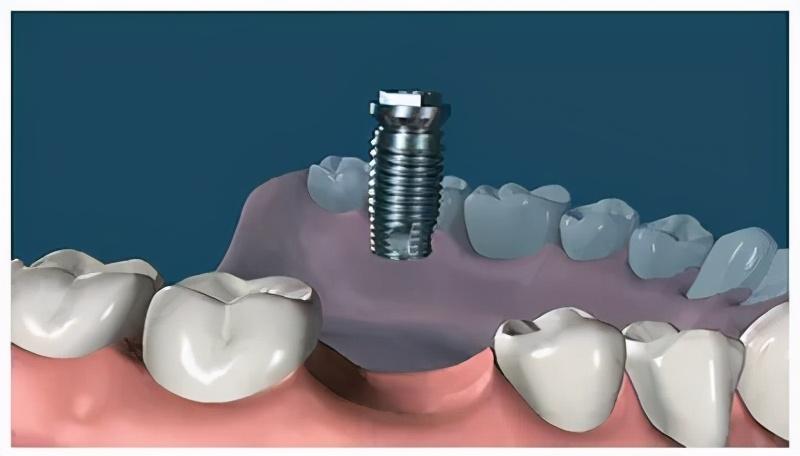

種植牙,全稱為人工種植牙,分成三個部分:種植體(人工牙根)、基臺(連接體)和牙冠(牙齒)。

種植體是一種高度精密的螺絲構(gòu)造,它外部的螺紋和微表面結(jié)構(gòu)與牙床骨接觸,引導(dǎo)牙床骨細(xì)胞生長到種植體表面,以達(dá)到種植體與牙床骨充分結(jié)合,增強(qiáng)其咀嚼力量及穩(wěn)定性能的目的。

確定能手術(shù)后,才會診斷取模、制定種植牙方案。(第一次大約1個多小時)然后正式開始種植牙手術(shù)。在牙槽骨上制備一個孔,植入人工種植體。將牙骨床內(nèi)嚴(yán)密縫合,大約一個星期后可以拆線(這次大概7--10天)。

注明:此植體只是模擬位置,不做確切種植位置。